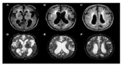

2.1.1. Magnetic Resonance Image (MRI)

2.1.2. Computed Tomography (CT)